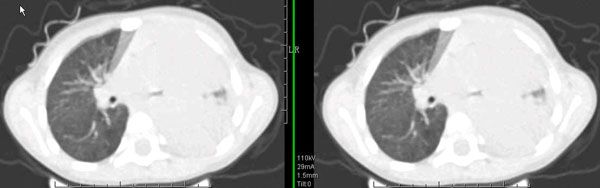

男孩,4岁,发热咳嗽4天。

下面补充ct图片:

此病人是我接手的,发热、咳嗽来做胸透,透视见左侧肺野大部密实,纵隔、心影明显左移,呼吸示纵隔摆动、膈肌矛盾运动(透视下采集了几幅图片),左肺动度明显减弱。询问病人家长,没有吃花生米等呛咳史。由于其影像特征明显,当时诊断:考虑左侧支气管异物并阻塞性肺不张、肺炎。

病人去上级医院支气管镜取出了异物。今天询问上级医院耳鼻喉科主任(是我同学),得知病人异物为胶冻样合并有少许白色粉末,后小儿说晚上喝药片时呛咳过,考虑当时为药片阻塞;另外支气管镜检发现小儿左侧支气管发育略窄,经住院抗炎治疗,现病人基本康复。

多谢各位关注及精彩点评!追踪病人结果时才知道还做过ct检查!对不起!有点晚了,刚刚下载,上传供大家参考!